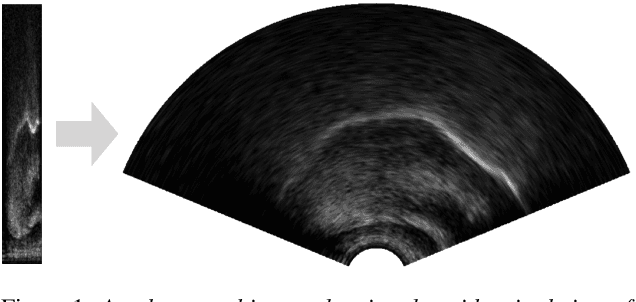

Abstract:Ultrasound tongue imaging is used to visualise the intra-oral articulators during speech production. It is utilised in a range of applications, including speech and language therapy and phonetics research. Ultrasound and speech audio are recorded simultaneously, and in order to correctly use this data, the two modalities should be correctly synchronised. Synchronisation is achieved using specialised hardware at recording time, but this approach can fail in practice resulting in data of limited usability. In this paper, we address the problem of automatically synchronising ultrasound and audio after data collection. We first investigate the tolerance of expert ultrasound users to synchronisation errors in order to find the thresholds for error detection. We use these thresholds to define accuracy scoring boundaries for evaluating our system. We then describe our approach for automatic synchronisation, which is driven by a self-supervised neural network, exploiting the correlation between the two signals to synchronise them. We train our model on data from multiple domains with different speaker characteristics, different equipment, and different recording environments, and achieve an accuracy >92.4% on held-out in-domain data. Finally, we introduce a novel resource, the Cleft dataset, which we gathered with a new clinical subgroup and for which hardware synchronisation proved unreliable. We apply our model to this out-of-domain data, and evaluate its performance subjectively with expert users. Results show that users prefer our model's output over the original hardware output 79.3% of the time. Our results demonstrate the strength of our approach and its ability to generalise to data from new domains.

Abstract:We investigate multi-speaker speech recognition from ultrasound images of the tongue and video images of the lips. We train our systems on imaging data from modal speech, and evaluate on matched test sets of two speaking modes: silent and modal speech. We observe that silent speech recognition from imaging data underperforms compared to modal speech recognition, likely due to a speaking-mode mismatch between training and testing. We improve silent speech recognition performance using techniques that address the domain mismatch, such as fMLLR and unsupervised model adaptation. We also analyse the properties of silent and modal speech in terms of utterance duration and the size of the articulatory space. To estimate the articulatory space, we compute the convex hull of tongue splines, extracted from ultrasound tongue images. Overall, we observe that the duration of silent speech is longer than that of modal speech, and that silent speech covers a smaller articulatory space than modal speech. Although these two properties are statistically significant across speaking modes, they do not directly correlate with word error rates from speech recognition.

Abstract:Speech sound disorders are a common communication impairment in childhood. Because speech disorders can negatively affect the lives and the development of children, clinical intervention is often recommended. To help with diagnosis and treatment, clinicians use instrumented methods such as spectrograms or ultrasound tongue imaging to analyse speech articulations. Analysis with these methods can be laborious for clinicians, therefore there is growing interest in its automation. In this paper, we investigate the contribution of ultrasound tongue imaging for the automatic detection of speech articulation errors. Our systems are trained on typically developing child speech and augmented with a database of adult speech using audio and ultrasound. Evaluation on typically developing speech indicates that pre-training on adult speech and jointly using ultrasound and audio gives the best results with an accuracy of 86.9%. To evaluate on disordered speech, we collect pronunciation scores from experienced speech and language therapists, focusing on cases of velar fronting and gliding of /r/. The scores show good inter-annotator agreement for velar fronting, but not for gliding errors. For automatic velar fronting error detection, the best results are obtained when jointly using ultrasound and audio. The best system correctly detects 86.6% of the errors identified by experienced clinicians. Out of all the segments identified as errors by the best system, 73.2% match errors identified by clinicians. Results on automatic gliding detection are harder to interpret due to poor inter-annotator agreement, but appear promising. Overall findings suggest that automatic detection of speech articulation errors has potential to be integrated into ultrasound intervention software for automatically quantifying progress during speech therapy.

Abstract:We present the Tongue and Lips corpus (TaL), a multi-speaker corpus of audio, ultrasound tongue imaging, and lip videos. TaL consists of two parts: TaL1 is a set of six recording sessions of one professional voice talent, a male native speaker of English; TaL80 is a set of recording sessions of 81 native speakers of English without voice talent experience. Overall, the corpus contains 24 hours of parallel ultrasound, video, and audio data, of which approximately 13.5 hours are speech. This paper describes the corpus and presents benchmark results for the tasks of speech recognition, speech synthesis (articulatory-to-acoustic mapping), and automatic synchronisation of ultrasound to audio. The TaL corpus is publicly available under the CC BY-NC 4.0 license.

Abstract:We investigate the automatic processing of child speech therapy sessions using ultrasound visual biofeedback, with a specific focus on complementing acoustic features with ultrasound images of the tongue for the tasks of speaker diarization and time-alignment of target words. For speaker diarization, we propose an ultrasound-based time-domain signal which we call estimated tongue activity. For word-alignment, we augment an acoustic model with low-dimensional representations of ultrasound images of the tongue, learned by a convolutional neural network. We conduct our experiments using the Ultrasuite repository of ultrasound and speech recordings for child speech therapy sessions. For both tasks, we observe that systems augmented with ultrasound data outperform corresponding systems using only the audio signal.

Abstract:We introduce UltraSuite, a curated repository of ultrasound and acoustic data, collected from recordings of child speech therapy sessions. This release includes three data collections, one from typically developing children and two from children with speech sound disorders. In addition, it includes a set of annotations, some manual and some automatically produced, and software tools to process, transform and visualise the data.

Abstract:Audiovisual synchronisation is the task of determining the time offset between speech audio and a video recording of the articulators. In child speech therapy, audio and ultrasound videos of the tongue are captured using instruments which rely on hardware to synchronise the two modalities at recording time. Hardware synchronisation can fail in practice, and no mechanism exists to synchronise the signals post hoc. To address this problem, we employ a two-stream neural network which exploits the correlation between the two modalities to find the offset. We train our model on recordings from 69 speakers, and show that it correctly synchronises 82.9% of test utterances from unseen therapy sessions and unseen speakers, thus considerably reducing the number of utterances to be manually synchronised. An analysis of model performance on the test utterances shows that directed phone articulations are more difficult to automatically synchronise compared to utterances containing natural variation in speech such as words, sentences, or conversations.

Abstract:Ultrasound tongue imaging (UTI) provides a convenient way to visualize the vocal tract during speech production. UTI is increasingly being used for speech therapy, making it important to develop automatic methods to assist various time-consuming manual tasks currently performed by speech therapists. A key challenge is to generalize the automatic processing of ultrasound tongue images to previously unseen speakers. In this work, we investigate the classification of phonetic segments (tongue shapes) from raw ultrasound recordings under several training scenarios: speaker-dependent, multi-speaker, speaker-independent, and speaker-adapted. We observe that models underperform when applied to data from speakers not seen at training time. However, when provided with minimal additional speaker information, such as the mean ultrasound frame, the models generalize better to unseen speakers.